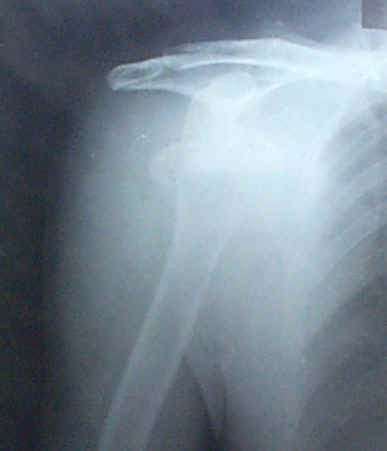

病例:赖友信

赖友信,男,出生于1956年12月12日,住江西省万载县三兴乡红旗村12组。1999年6月13日骑摩托车时不小心跌入沟里,右手不能动,即时请我去医治。经我诊断右手肩碗全部脱位,肱骨插入腋窝内,第一次接抖不成功,送去三兴卫生院摄片诊断,右手肱骨骨折,严重脱位并有一小块肱骨分裂离位。回来后经三次接抖才复位。贴一张大号和一张小号膏药,稍余用布带定位几天,15天后患者能骑摩托车。第二次换一张大号膏药,可以说恢复得完好如初。